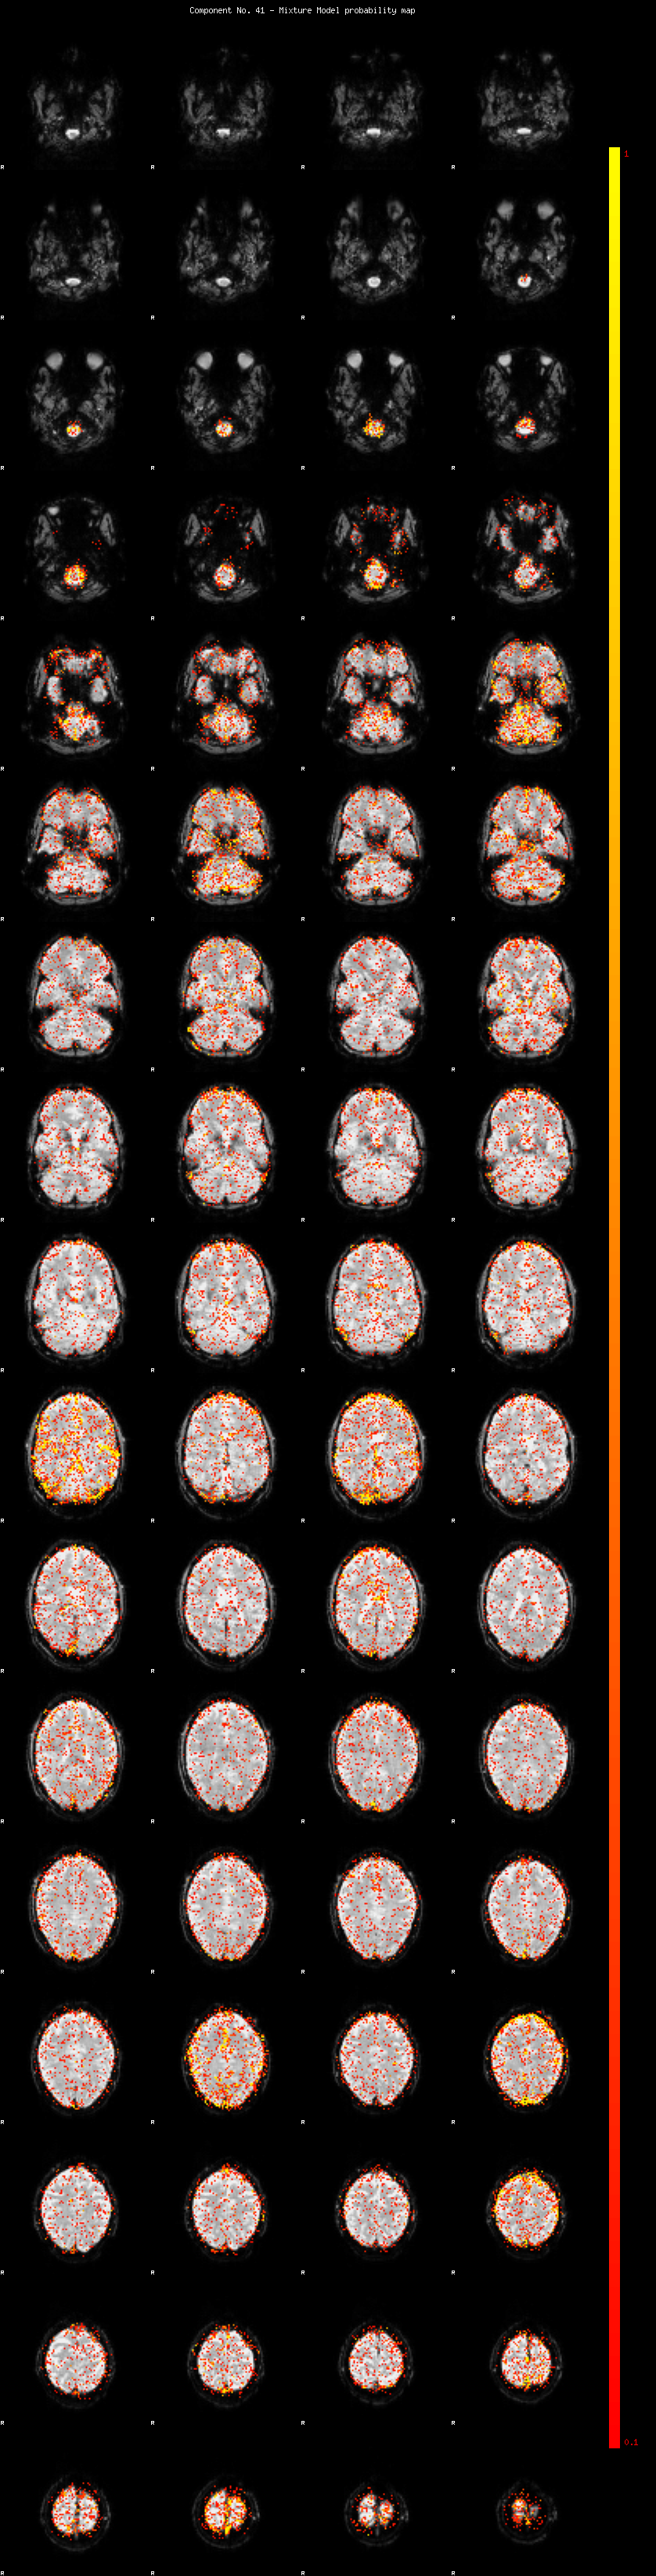

IC_41 Mixture Model fit

Means : -0.000000 2.431930 -2.314082

Vars : 1.000000 1.829558 1.497589

Prop. : 0.927453 0.039751 0.032796